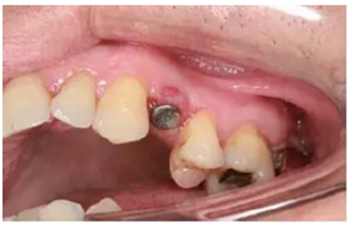

種植完成

種植完成后可以通過拍攝曲面體層或是根尖片來確認(rèn)種植體的植入情況,并作為資料加以保存。

種植手術(shù)完成2周后進(jìn)行拆線??梢钥闯鲕浗M織愈合良好。

圖7 曲面體層片

圖8 拆線時(shí)的口內(nèi)照片